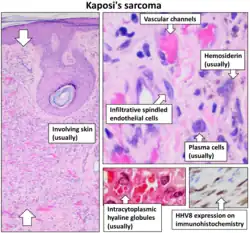

Pathology

Despite its name, in general it is not considered a true sarcoma,[27][28] which is a tumor arising from mesenchymal tissue. The histogenesis of KS remains controversial.[29] KS may arise as a cancer of lymphatic endothelium[30] and forms vascular channels that fill with blood cells, giving the tumor its characteristic bruise-like appearance. KSHV proteins are uniformly detected in KS cancer cells.

KS lesions contain tumor cells with a characteristic abnormal elongated shape, called spindle cells. The most typical feature of Kaposi sarcoma is the presence of spindle cells forming slits containing red blood cells. Mitotic activity is only moderate and pleomorphism is usually absent.[31] The tumor is highly vascular, containing abnormally dense and irregular blood vessels, which leak red blood cells into the surrounding tissue and give the tumor its dark color. Inflammation around the tumor may produce swelling and pain. Variously sized PAS positive hyaline bodies are often seen in the cytoplasm or sometimes extracellularly.

The spindle cells of Kaposi sarcoma differentiate toward endothelial cells, probably of lymph vessel rather than blood vessel origin.[32] The consistent immunoreactivity for podoplanin supports the lymphatic nature of the lesion.

Micrograph of a Kaposi sarcoma showing the characteristic spindle cells, high vascularity, and intracellular hyaline globs. H&E stain.

Micrograph of a Kaposi sarcoma showing the characteristic spindle cells, high vascularity, and intracellular hyaline globs. H&E stain. -